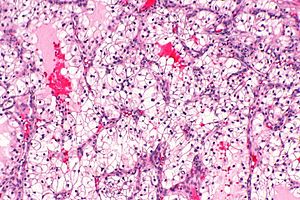

In VHL these have distinct morphology:

- Clear cells[9] - unusual in neuroendocrine tumours otherwise.

- Fibrosis. (???)